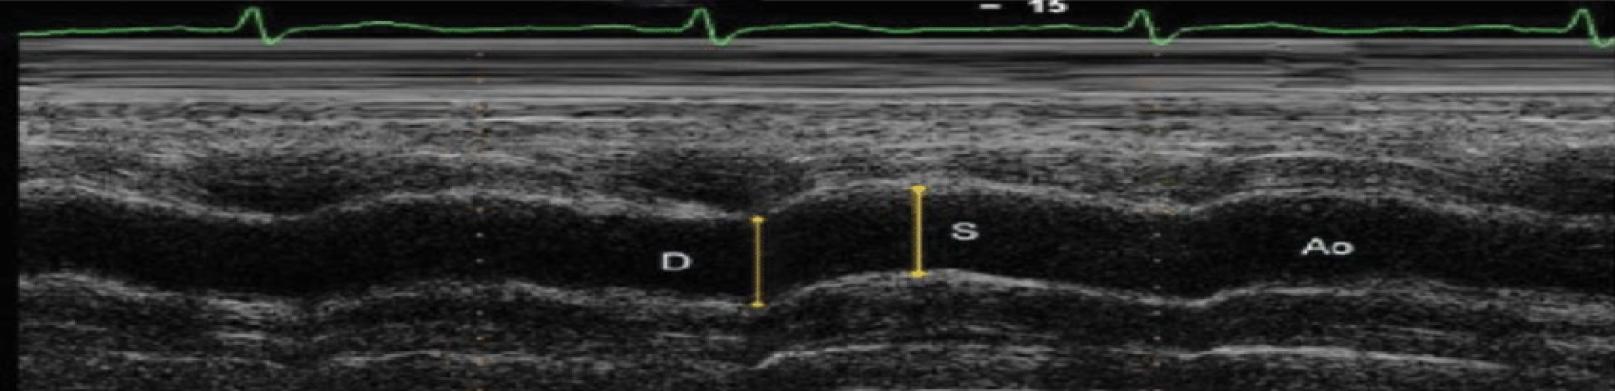

Figure 1